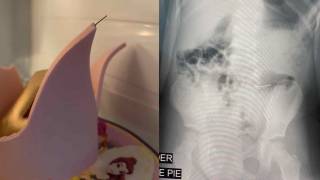

Niñas ingieren metal al morder un pastel de fondant y acaban en el hospital